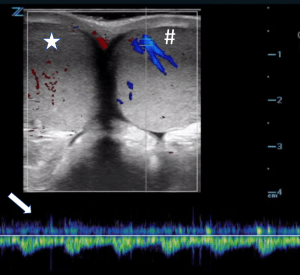

All POCUS images were obtained on a Zonare Z.one ultrasound using a linear high frequency transducer and scrotal presets. Images were obtained on the unaffected side first, both in B-mode and color Doppler, and adequate depth and gain were verified before proceeding to the affected testis. After B-mode and color Doppler imaging were obtained in sagittal orientation on both testes, a “buddy view” or transverse color Doppler image of both testes in the same image was obtained. Spectral Doppler was used in a number of cases (Figure 1). Spectral Doppler is a useful modality to evaluate resistance to forward flow, as discussed further in our cases.

Figure 1. Spectral Doppler image of normal, low-resistance testicular arterial blood flow. Note the homogenous echogenicity and low velocity blood flow that consistently stays above the baseline.